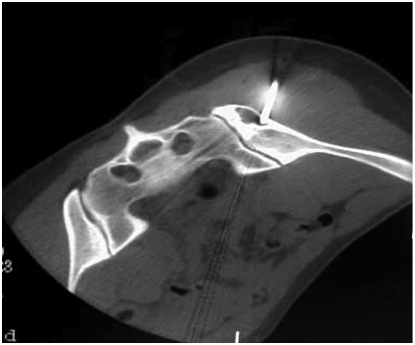

А.А. Жантурина, к.м.н. врач высшей категории Грыжа межпозвоночного диска – это дегенеративно-дистрофическое...

Межпозвоночная грыжа является заболеванием позвоночника, при котором деформированный позвоночный диск смещается, выходя...